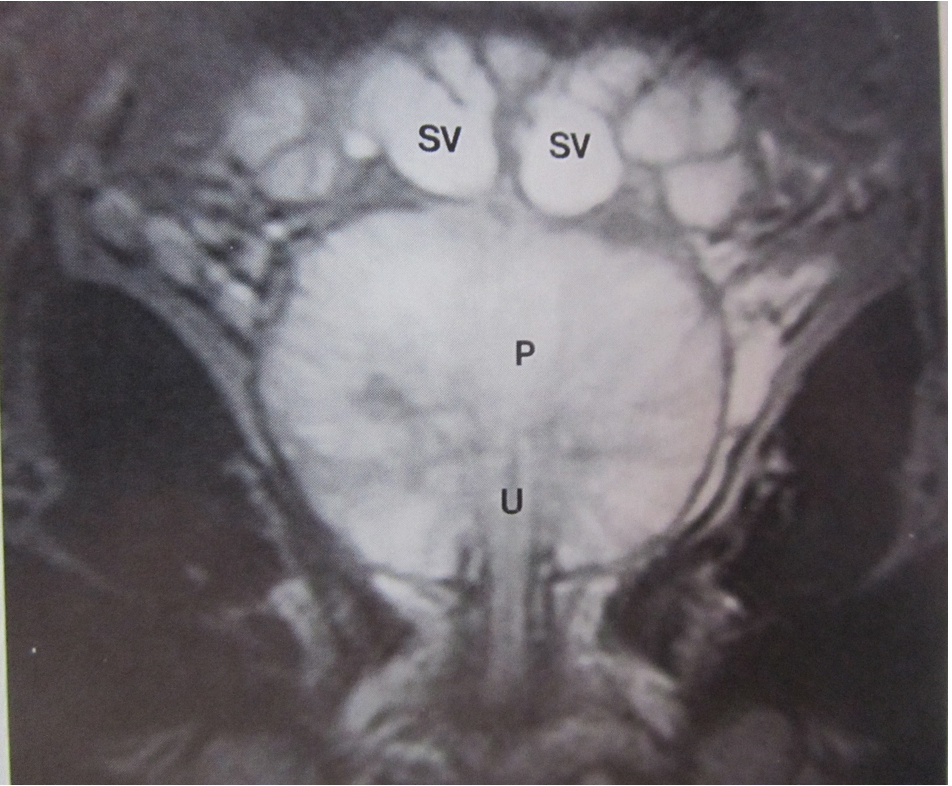

What do the letters represent?

SV: seminal vesicles

P: Prostate

U: Urethra